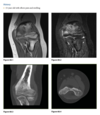

Sagittal proton-density (Fig. 2.14.1)

and fast spin-echo, T2-weighted fat-suppressed

(Fig. 2.14.2) MR images show an area of increased

signal intensity within the anterior cruciate ligament

(ACL), the so-called pseudo-mass (arrows); nonvisual-

ization of the normal ACL fibers; and a joint effusion.

A sagittal fast spin-echo, T2-weighted fat-suppressed

MR image through the lateral joint compartment

(Fig. 2.14.3) shows high-signal-intensity areas in the

subchondral regions of the midportion of the lateral femoral condyle and the posterolateral tibial plateau,

the so-called “kissing contusions”

Full thickness tear of the ACL

Conventional radiographic findings of an ACL

tear include avulsion fractures from the femoral or

tibial attachment of the ACL (Fig. 2.14.4, arrow), the

Segond fracture (Fig. 2.14.4, arrowhead), or a deep

lateral sulcus sign (Fig. 2.14.5, arrow).

MRI features of the torn ACL include an irregular

or wavy contour with decreased angulation on the

sagittal images (i.e., “lying down” or vertically ori-

ented ACL), increased signal intensity on all MRI

sequences in the region of the ACL (i.e., so-called

“pseudo-mass”), posterior displacement of the lateral

meniscus (i.e., “uncovered lateral meniscus” sign),

loss of the normal obtuse curvature with increased

angulation of the posterior cruciate ligament, undu-

lation of the patellar tendon, and the “empty notch”

sign, which is also seen on arthroscopy.

Bone

impaction from transient subluxation results in

the characteristic osseous contusions involving the posterolateral tibial plateau and midportion of the

lateral femoral condyle (i.e., “kissing contusions”).